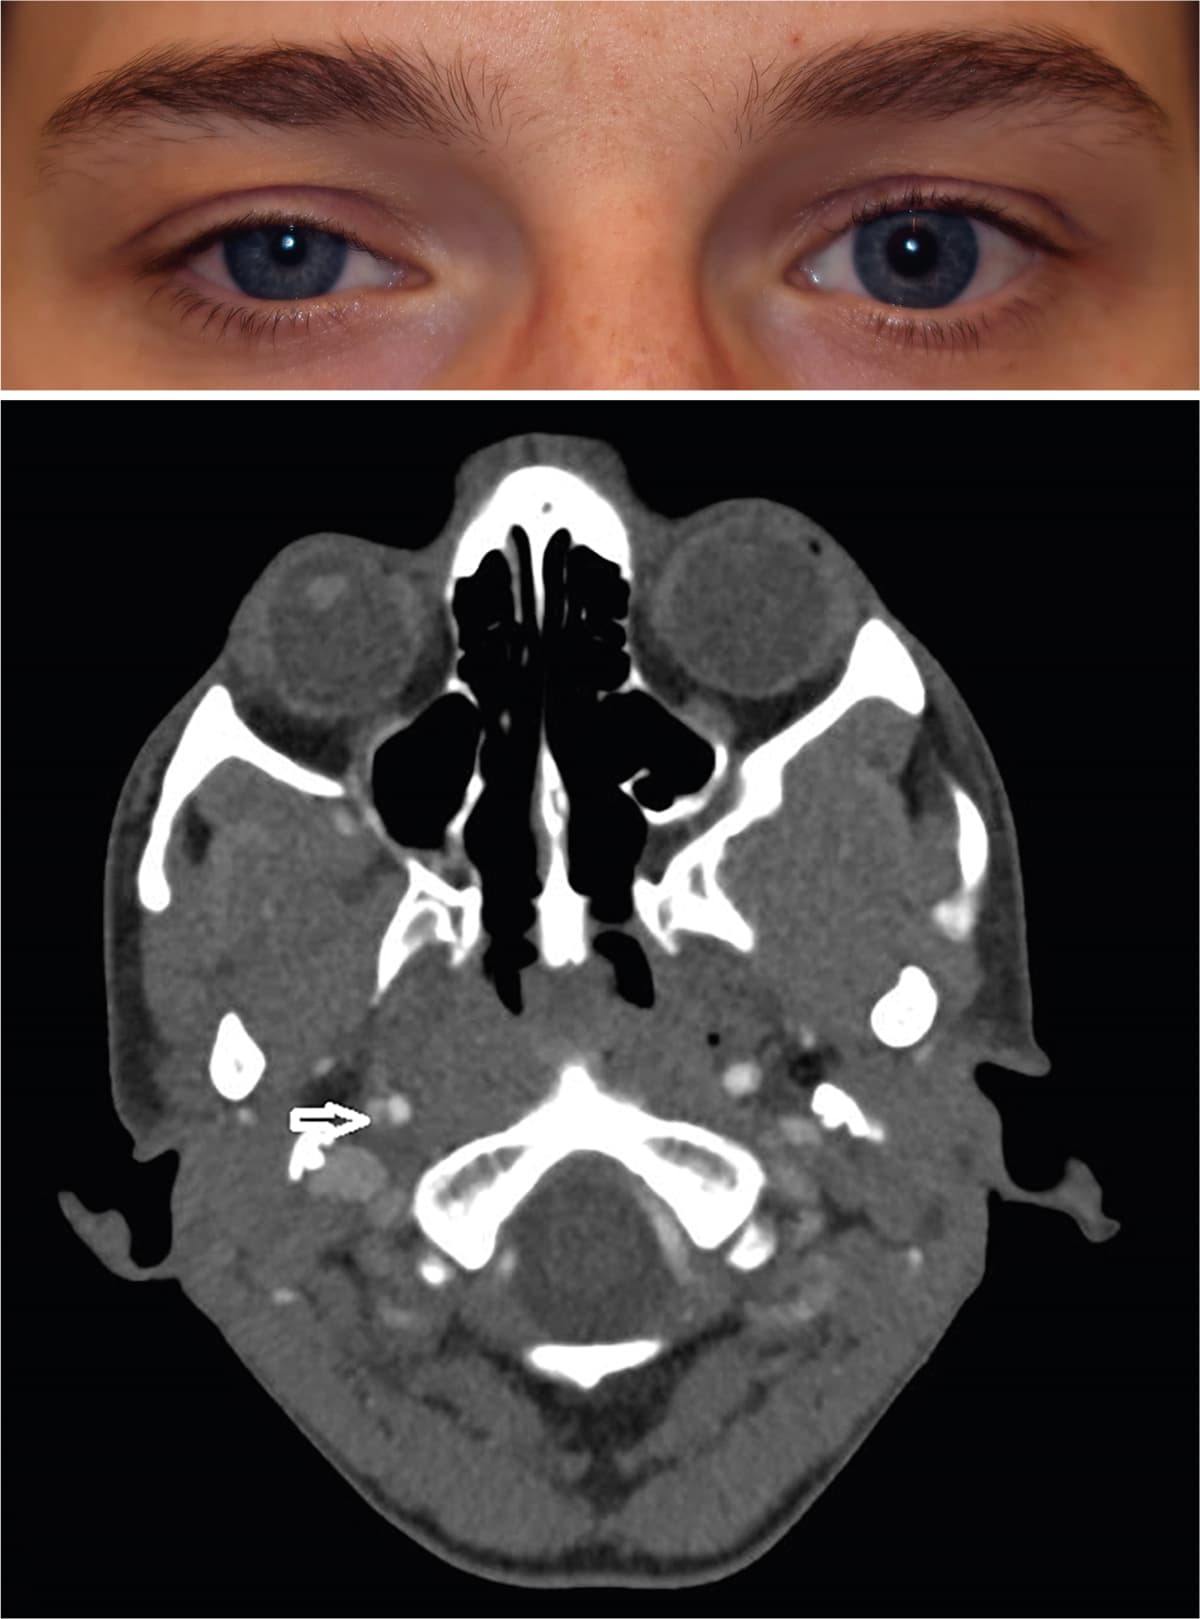

En rask 26-årig kvinde fik højresidigt hængende øjenlåg, pupildifference samt skulder- og nakkesmerter efter styrketræning uden hoved-/nakketraume. Objektiv fandt man højresidig ptose og miosis. Ved test med apraclonidin 0,5% sås begyndende ophævelse af ptosen efter 10 min. Der var mistanke om Horners syndrom, og der blev foretaget CT-angiografi af cerebrum og halskar, hvorved man så dissektion i den distale a. carotis interna. Der blev påbegyndt dobbeltpladehæmmerbehandling (acetylsalicylsyre samt clopidogrel) og planlagt kontrol efter tre måneder.

Horners syndrom defineres ved miosis, ptose og anhidriosis, som kan forårsages af en læsion af de sympatiske nervefibre (fra hypothalamus til hjernestammen, den øverste torakale medulla (C8-T2) og langs a. carotis til trigeminusnerven [1].

Miosis er som regel mild og mest udtalt i mørke. Ptosen er også mild og omfatter både nedre og øvre øjenlåg [1].